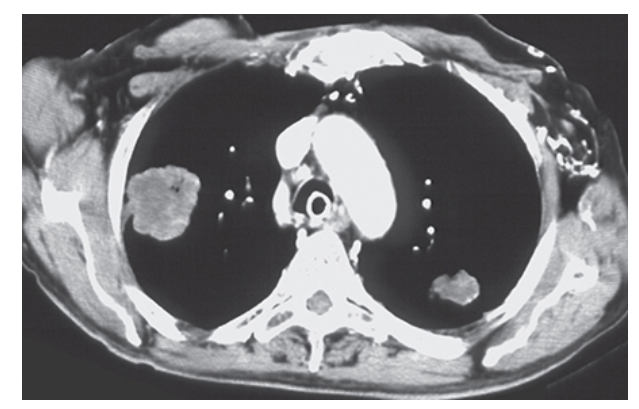

Pulmonary Metastatic Disease. CT of the chest with mediastinal windows demonstrating bilateral upper lobe masses with areas of low density representing necrosis.

Pulmonary Metastatic Disease. CT with lung window showing bilateral upper lobe masses with slightly irregular margins consistent with metastatic lesions.